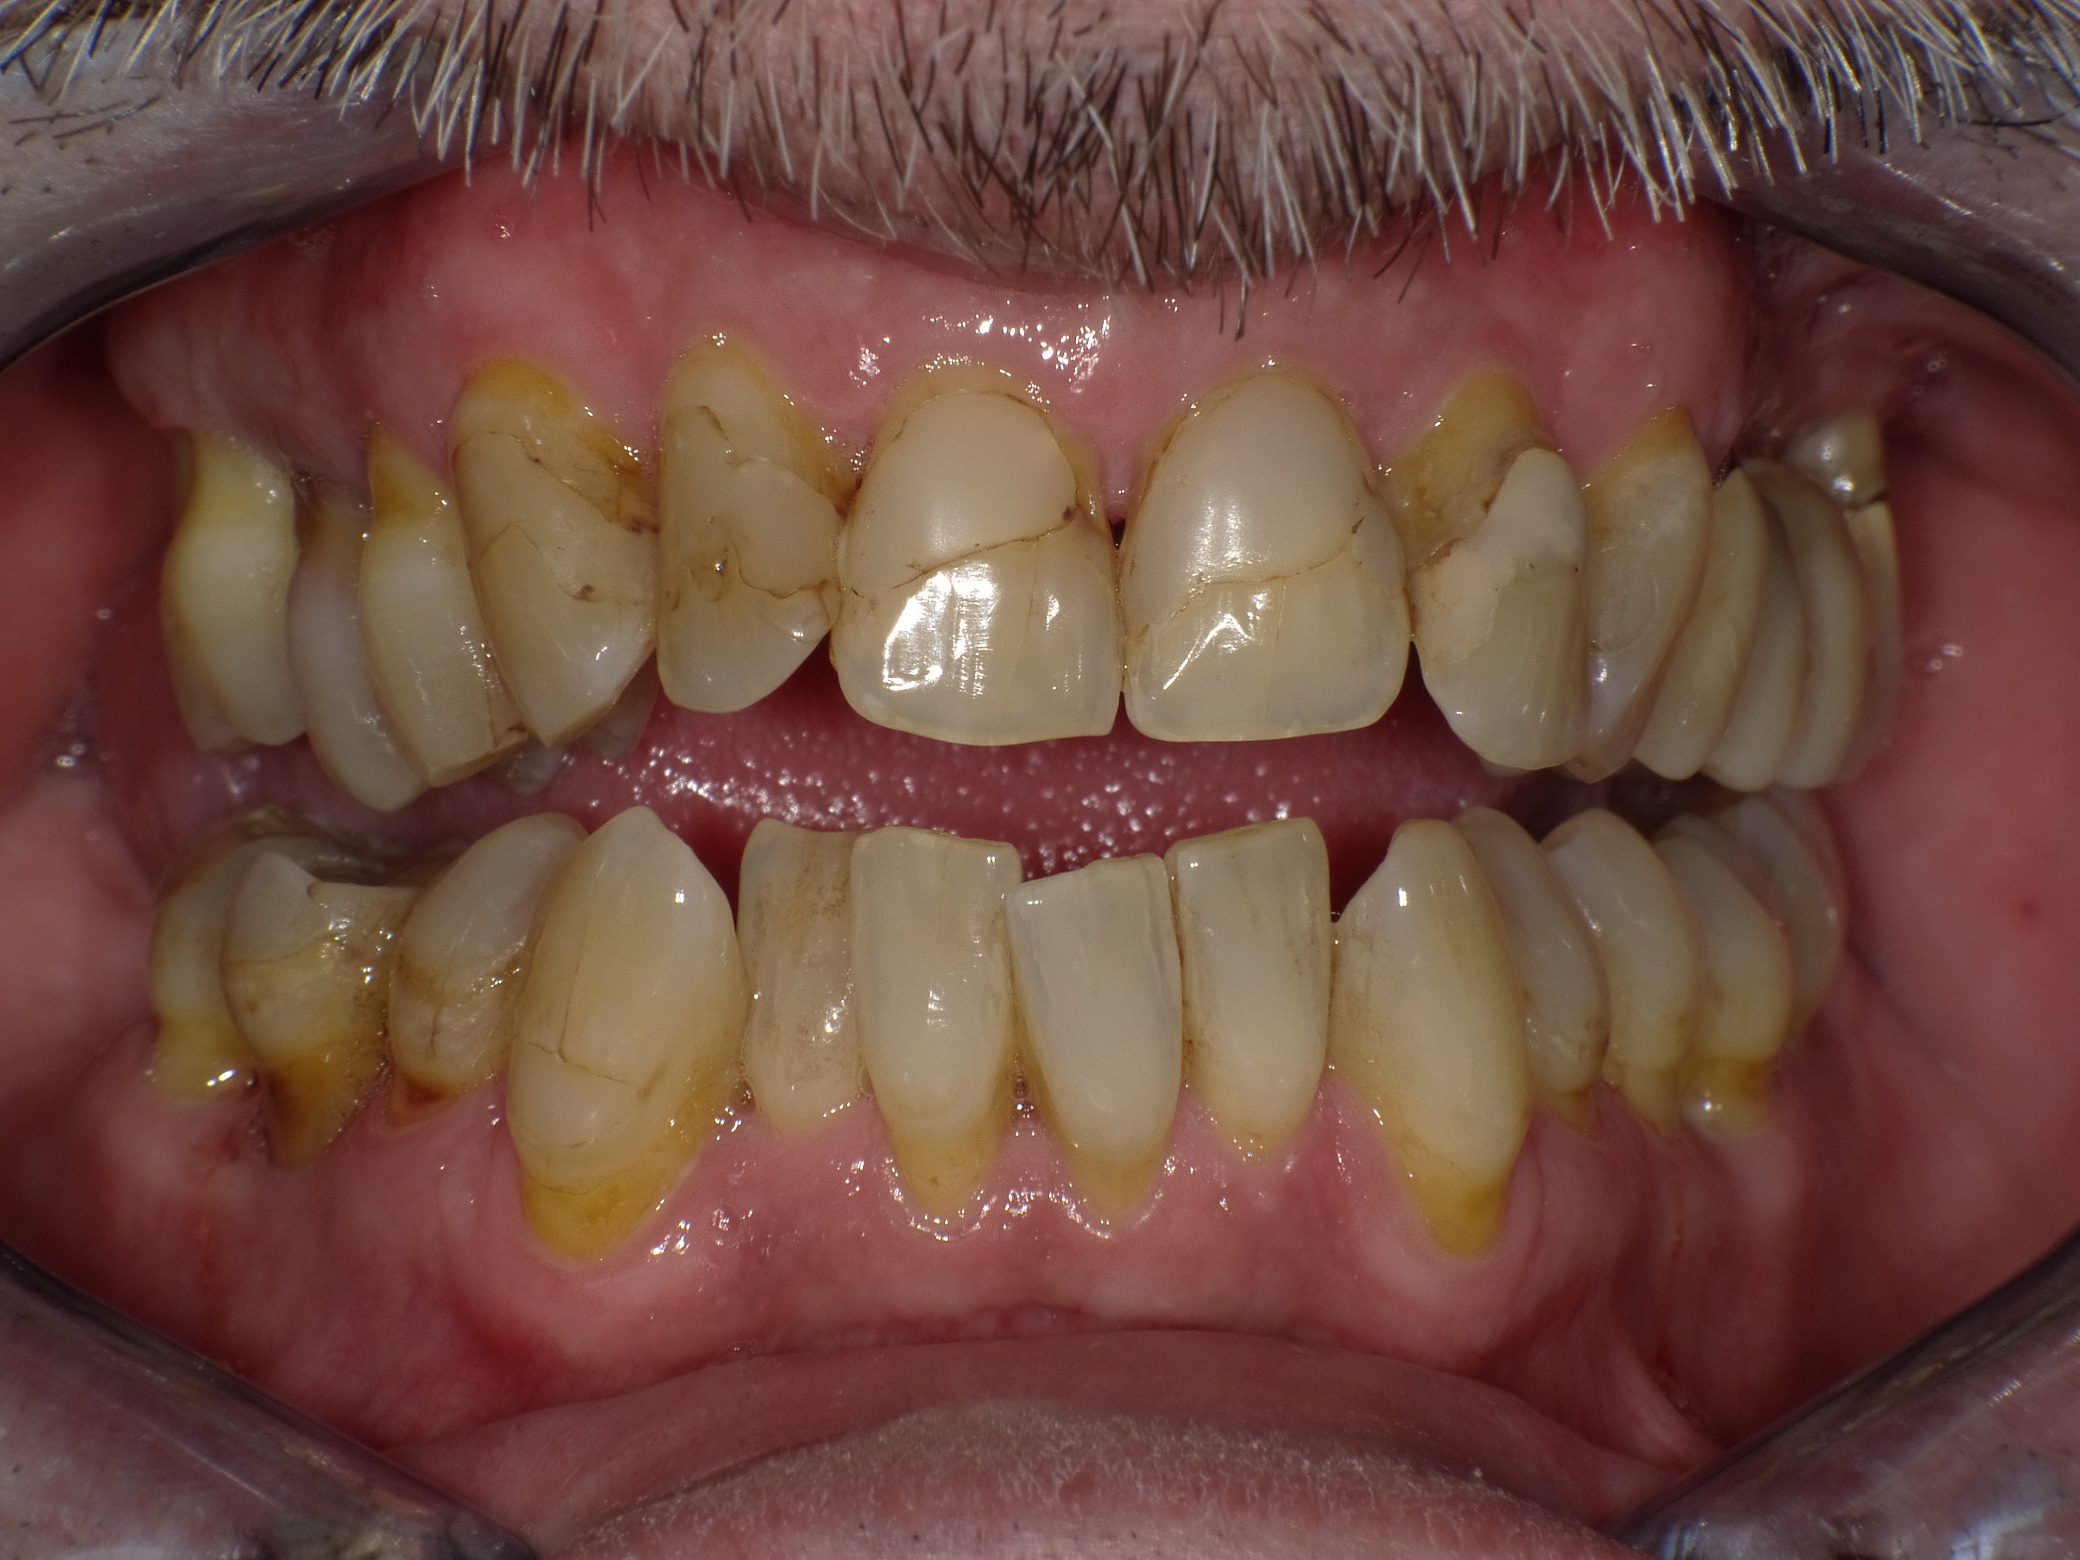

Unzufriedener Patient nach langjähriger Betreuung durch seinen "Hauszahnarzt" bei ihm im Dorf

Vorher: Unzufriedener Patient nach langjähriger Betreuung durch seinen "Hauszahnarzt" bei ihm im Dorf

Korrektur in 2 Langzeitterminen mit Vollkeramik

Nachher: Korrektur in 2 Langzeitterminen mit Vollkeramik